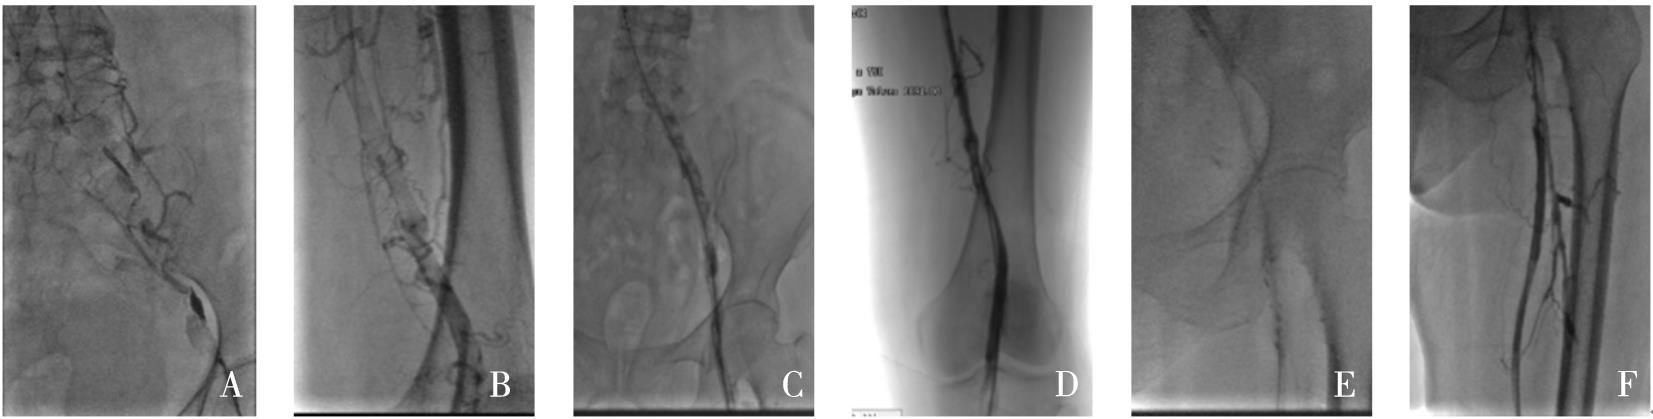

摘要:该文追踪1例低叶酸血症患者6年,观察患者体内血栓的动态演变过程。对该例患者进行了叶酸水平、同型半胱氨酸、维生素B12水平监测,同时监测患者的颈动脉超声、下肢动脉超声、头颅磁共振成像和磁共振血管成像,并获得患者的基因学检测结果。第1年,患者出现了左侧大脑中动脉皮质支闭塞(叶酸2.23 ng/mL)。第2年,患者出现了左下肢深静脉血栓(叶酸2.58 ng/mL)。第3年,患者出现左侧颈内动脉颅内段大部分闭塞(叶酸2.16 ng/mL)。第4年,患者出现右下肢深静脉血栓+左侧颈内动脉颅外段狭窄+右下肺静脉血栓形成(叶酸2.27 ng/mL),此时启动了补充叶酸治疗。第5年,患者未再新发血栓。采用DNA微阵列法检测发现,该例患者基因组中MTHFR基因677位为T/T纯合型(突变型)。第6年,患者死于肺炎。该类型突变的患者会出现低叶酸血症,导致快速侵袭性、全身动静脉多发性血栓,补充叶酸治疗可能有效。